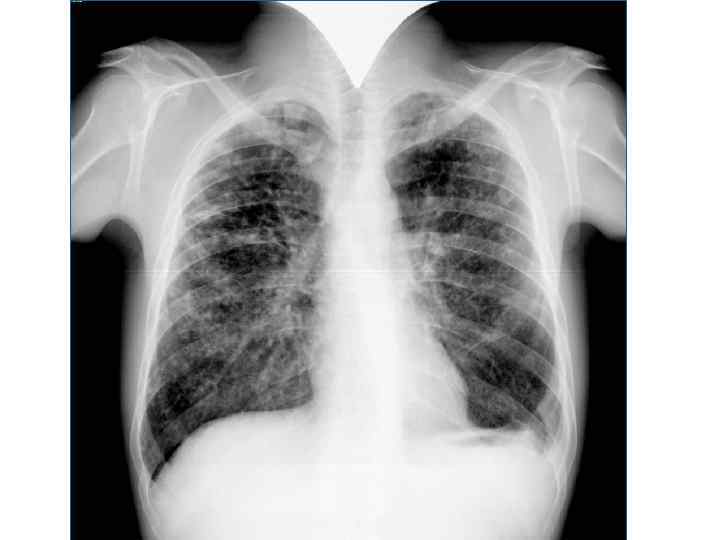

Рентгенологическая картина Спустя 10 -14 дней болезни появляются множественные мелкие / до 2 мм/ однотипные очаги на всем протяжении легких, создается впечатление о более массивной диссеминации в средних отделах. Очаги округлой формы, малой интенсивности, контуры нечеткие, часто расположены в виде цепочки вдоль сосудов. Сосудистый рисунок обеднен